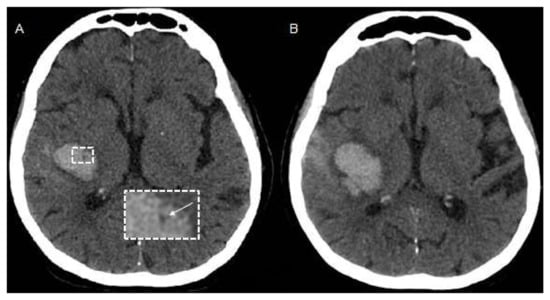

CT Perfusion (CTP) measures blood flow across brain capillaries (microcirculation) through the analysis of the first passage through cerebral vessels of an intravenous contrast bolus, using a tracer that remains intravascular since iodinated contrast does not cross the blood–brain barrier (BBB). CTP is a dynamic bolus-tracking technique based on repeated acquisition of a series of images before, during and after the injection of an intravenous contrast bolus. The role of CTP in identifying ICH etiology is currently very limited due to the obscuration of the underlying tissue by the extravasated blood leading to tissue destruction and anatomical distortion [18]. However, it has previously been demonstrated that peritumoral edematous CBV values are elevated in high grade gliomas and low in brain metastasis, suggesting the development of neoangiogenesis in the edema region surrounding high grade gliomas, related to infiltrative spreading of these lesions [19]. Therefore, as perihematomal edema is usually hypoperfused in spontaneous ICH [20], the occurrence of high perihematomal CBV levels can suggest that ICH is due to an underlying tumor (Figure 1) but this finding needs validation in larger studies. In addition, although CT Angiography can be considered the method of choice for rapid detection of ruptured vascular abnormalities [21], CTP pattern could better define the hemodynamic characteristics of any underlying brain arteriovenous malformation, providing different CTP profiles [22].

Figure 1.

Example of CT Perfusion in a patient with ICH due to malignancy. Non-contrast CT (NCCT) scan (A) and cerebral blood volume (CBV) map (B) in a patient with acute ICH due to the bleeding of an underlying high grade glioma located left frontal lobe and characterized by elevated CBV values in the perihematomal region (arrows).